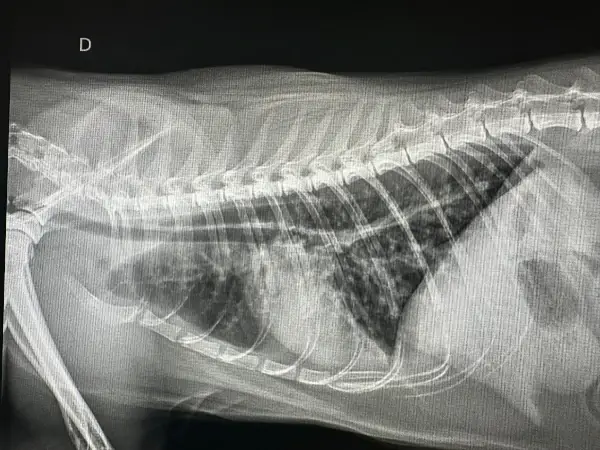

Problemas Respiratorios

especialidades felinas en vías bajas

Una de las causas más habituales son las enfermedades respiratorias de las vías bajas, entre las que destacan el asma felina y la bronquitis crónica felina.

Ambas patologías pueden parecerse mucho ya que las dos provocan tos, dificultad respiratoria y episodios de jadeo.

Por eso, en DeGatitos damos una gran importancia a realizar un diagnóstico preciso, que puede incluir radiografías, ecografía torácica, broncoscopia o lavado broncoalveolar, citología y PCR de enfermedades infecciosas.

Porque diferenciar correctamente entre asma y bronquitis crónica no solo cambia el pronóstico, sino que marca la diferencia en cómo tu gato vivirá con su enfermedad respiratoria.

Diagnóstico por Imagen: Radiología y Ecografía

El diagnóstico por imagen es fundamental en medicina felina moderna. Muchas enfermedades solo pueden diagnosticarse mediante visualización directa de órganos internos, y la capacidad de obtener imágenes de alta calidad determina la precisión del diagnóstico.

Radiología digital: Nuestro equipo de rayos X digital proporciona imágenes de alta resolución en segundos, con una fracción de la radiación de los sistemas analógicos tradicionales. Esto es especialmente importante en gatos, donde la exposición debe minimizarse por su menor tamaño corporal.

La radiografía es insustituible para:

- Evaluación de patología respiratoria (neumonía, asma, efusión pleural)

Realizamos estudios radiográficos con sedación mínima o sin sedación cuando es posible, priorizando el bienestar del paciente. En casos donde se requieren múltiples proyecciones o posiciones específicas, utilizamos sedación leve para evitar estrés y garantizar la calidad de las imágenes.